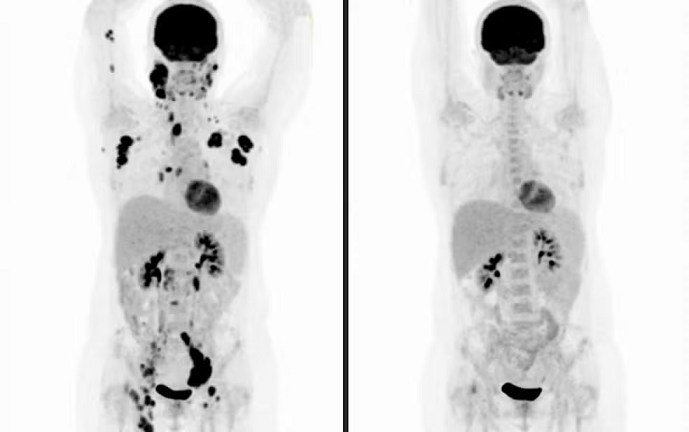

Até o momento, 20 pacientes foram tratados de forma individualizada e experimental com a terapia de células CAR-T, sendo que 14 deles continuam bem, de acordo com os médicos. Todos eram casos graves para os quais não havia mais opção terapêutica.